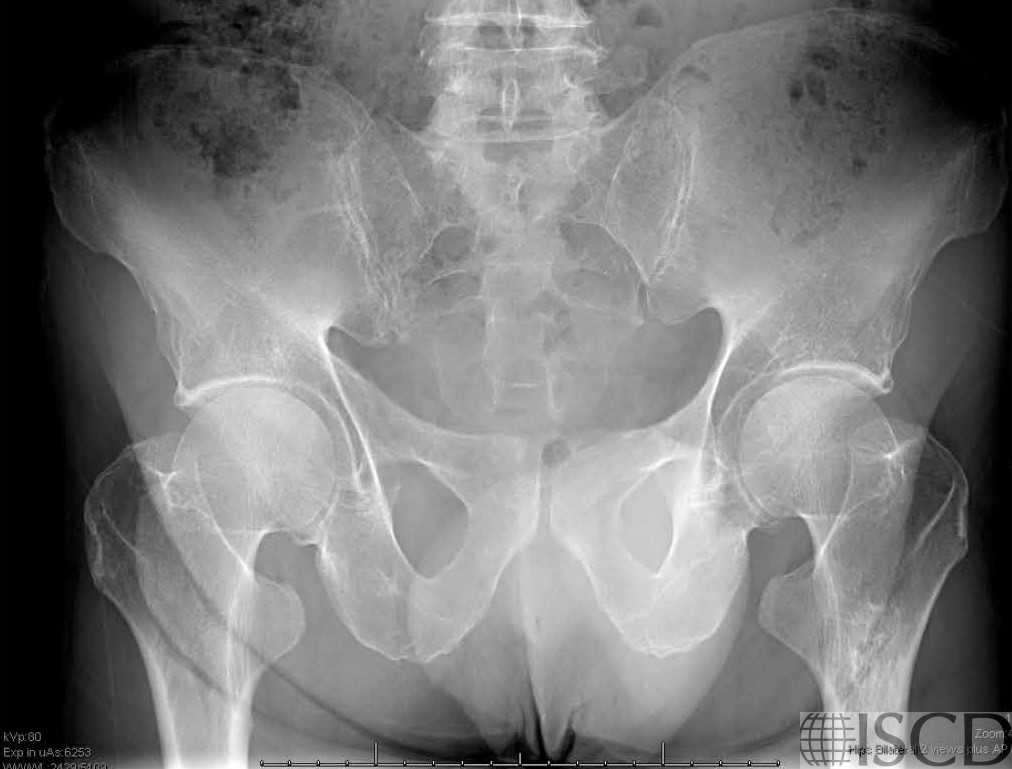

There is a black hole artifact over L4, therefore it was omitted from analysis. There are black hole-type artifacts over L4 and in the soft tissue.

This radiograph shows the tantalum clips overlying L4 that are responsible for the black hole artifact on the Hologic lumbar spine scan.

This Hologic lumbar spine DXA scan shows a black hole-type artifact over L4. Items like lead bullets and tantalum clips show up as “black”on Hologic scans. The accompanying radiograph shows the clips over L4. L4 is omitted because of overlying artifacts.